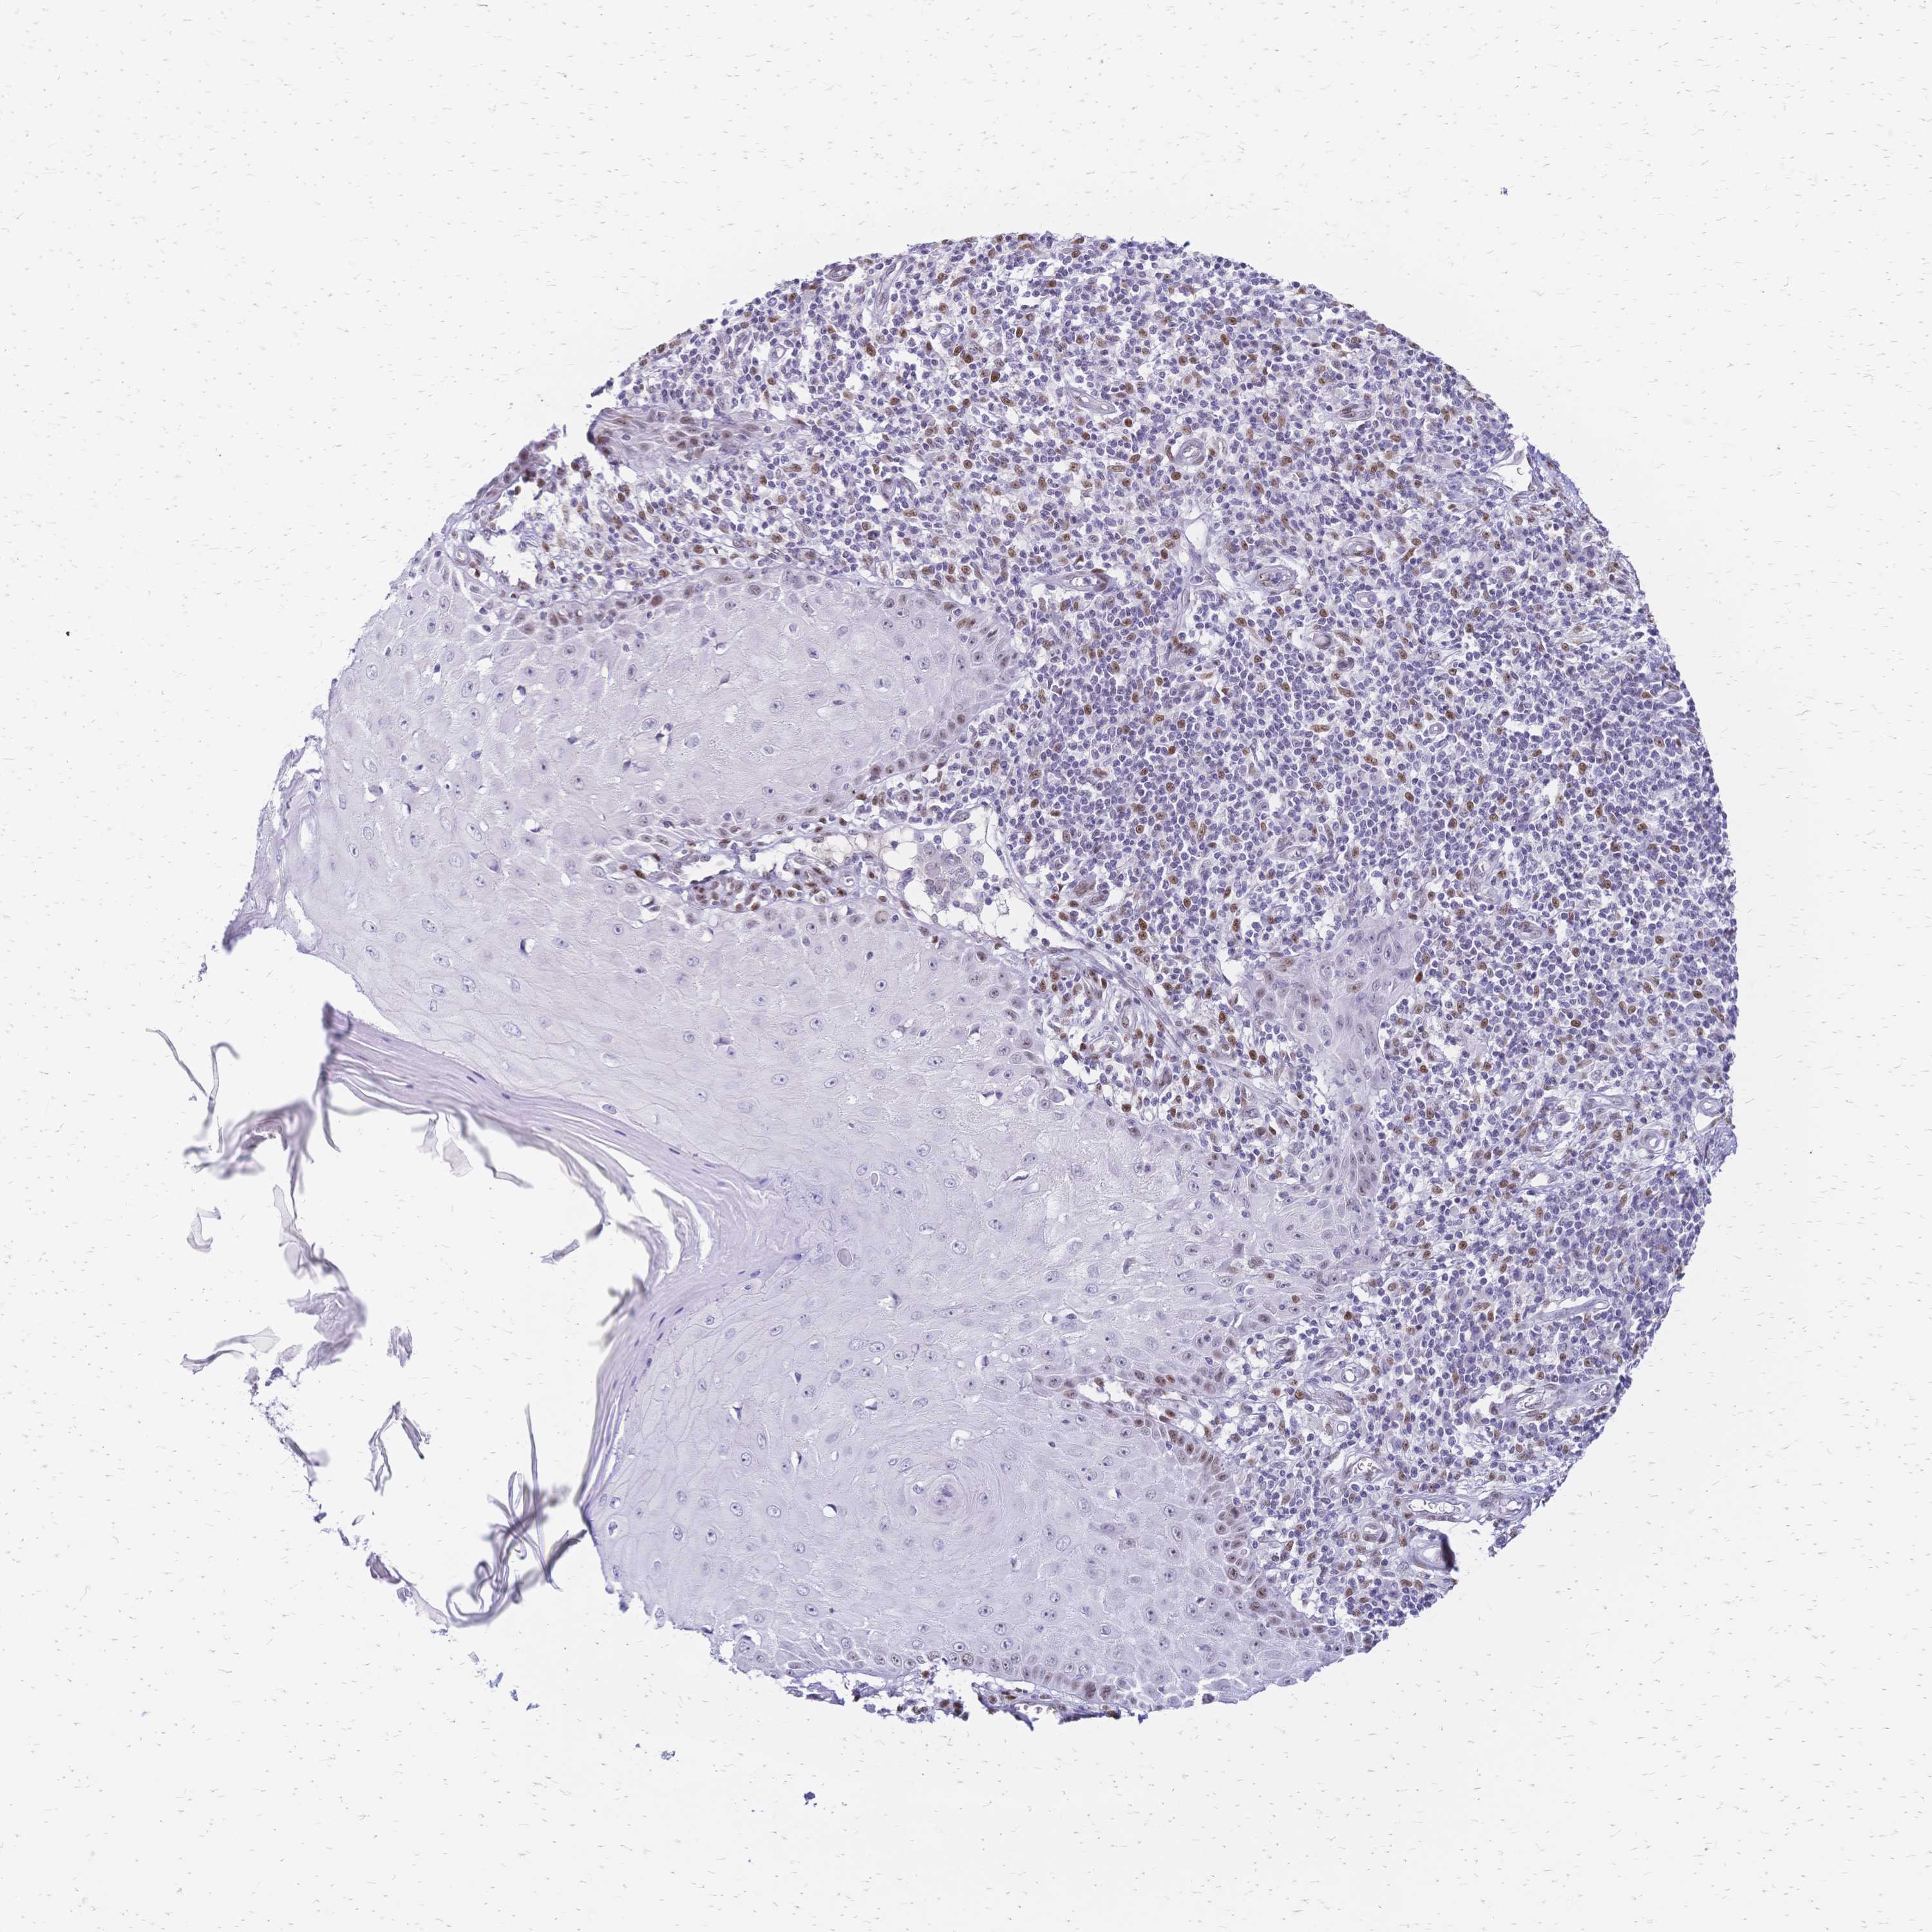

SKIN CANCER - Protein expressioni

A mouse-over function shows sample information and annotation data. Click on an image to view it in a full screen mode. Samples can be filtered based on level of antibody staining by selecting one or several of the following categories: high, medium, low and not detected. The assay and annotation is described here.

Antibody stainingi

Antibody staining in the annotated cell types in the current human tissue is reported as not detected, low, medium, or high, based on conventional immunohistochemistry profiling in selected tissues. This score is based on the combination of the staining intensity and fraction of stained cells.

Each image is clickable and will lead to virtual microscopy that enables deeper exploration of all samples and also displays staining intensity scores, fraction scores and subcellular localization as well as patient and tissue information for each sample.

Antibody CAB004300

Staining

Low

Weak

<25%

Nuclear

Basal cell carcinoma

Squamous cell carcinoma, NOS